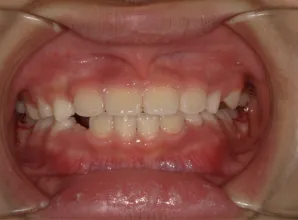

治療前①小1(7y2m):初診

*上顎前歯後方傾斜、上下唇の突出、口唇閉鎖不全傾向、コンケーブなし

| カウンセリング・診断結果 | 骨格的に下顎前方位で下顎骨も大きいタイプで、上の前歯が後ろに傾斜している受け口です。 顔立ちは上下唇が突出していて口唇閉鎖不全傾向がありますが、コンケーブにはなっていません(写真①)。 機能的に低位舌があり、今後受け口を助長する可能性があります。 受け口は、上顎骨の骨格的な前方向の成長を阻害し下顎が前へ強く成長していくため、骨格的な受け口が悪化し永久歯の咬合治療が難しくなり、症例によっては外科的な治療が必要になることがあるため早期に改善し骨格的な悪化を予防する説明をしました。 |